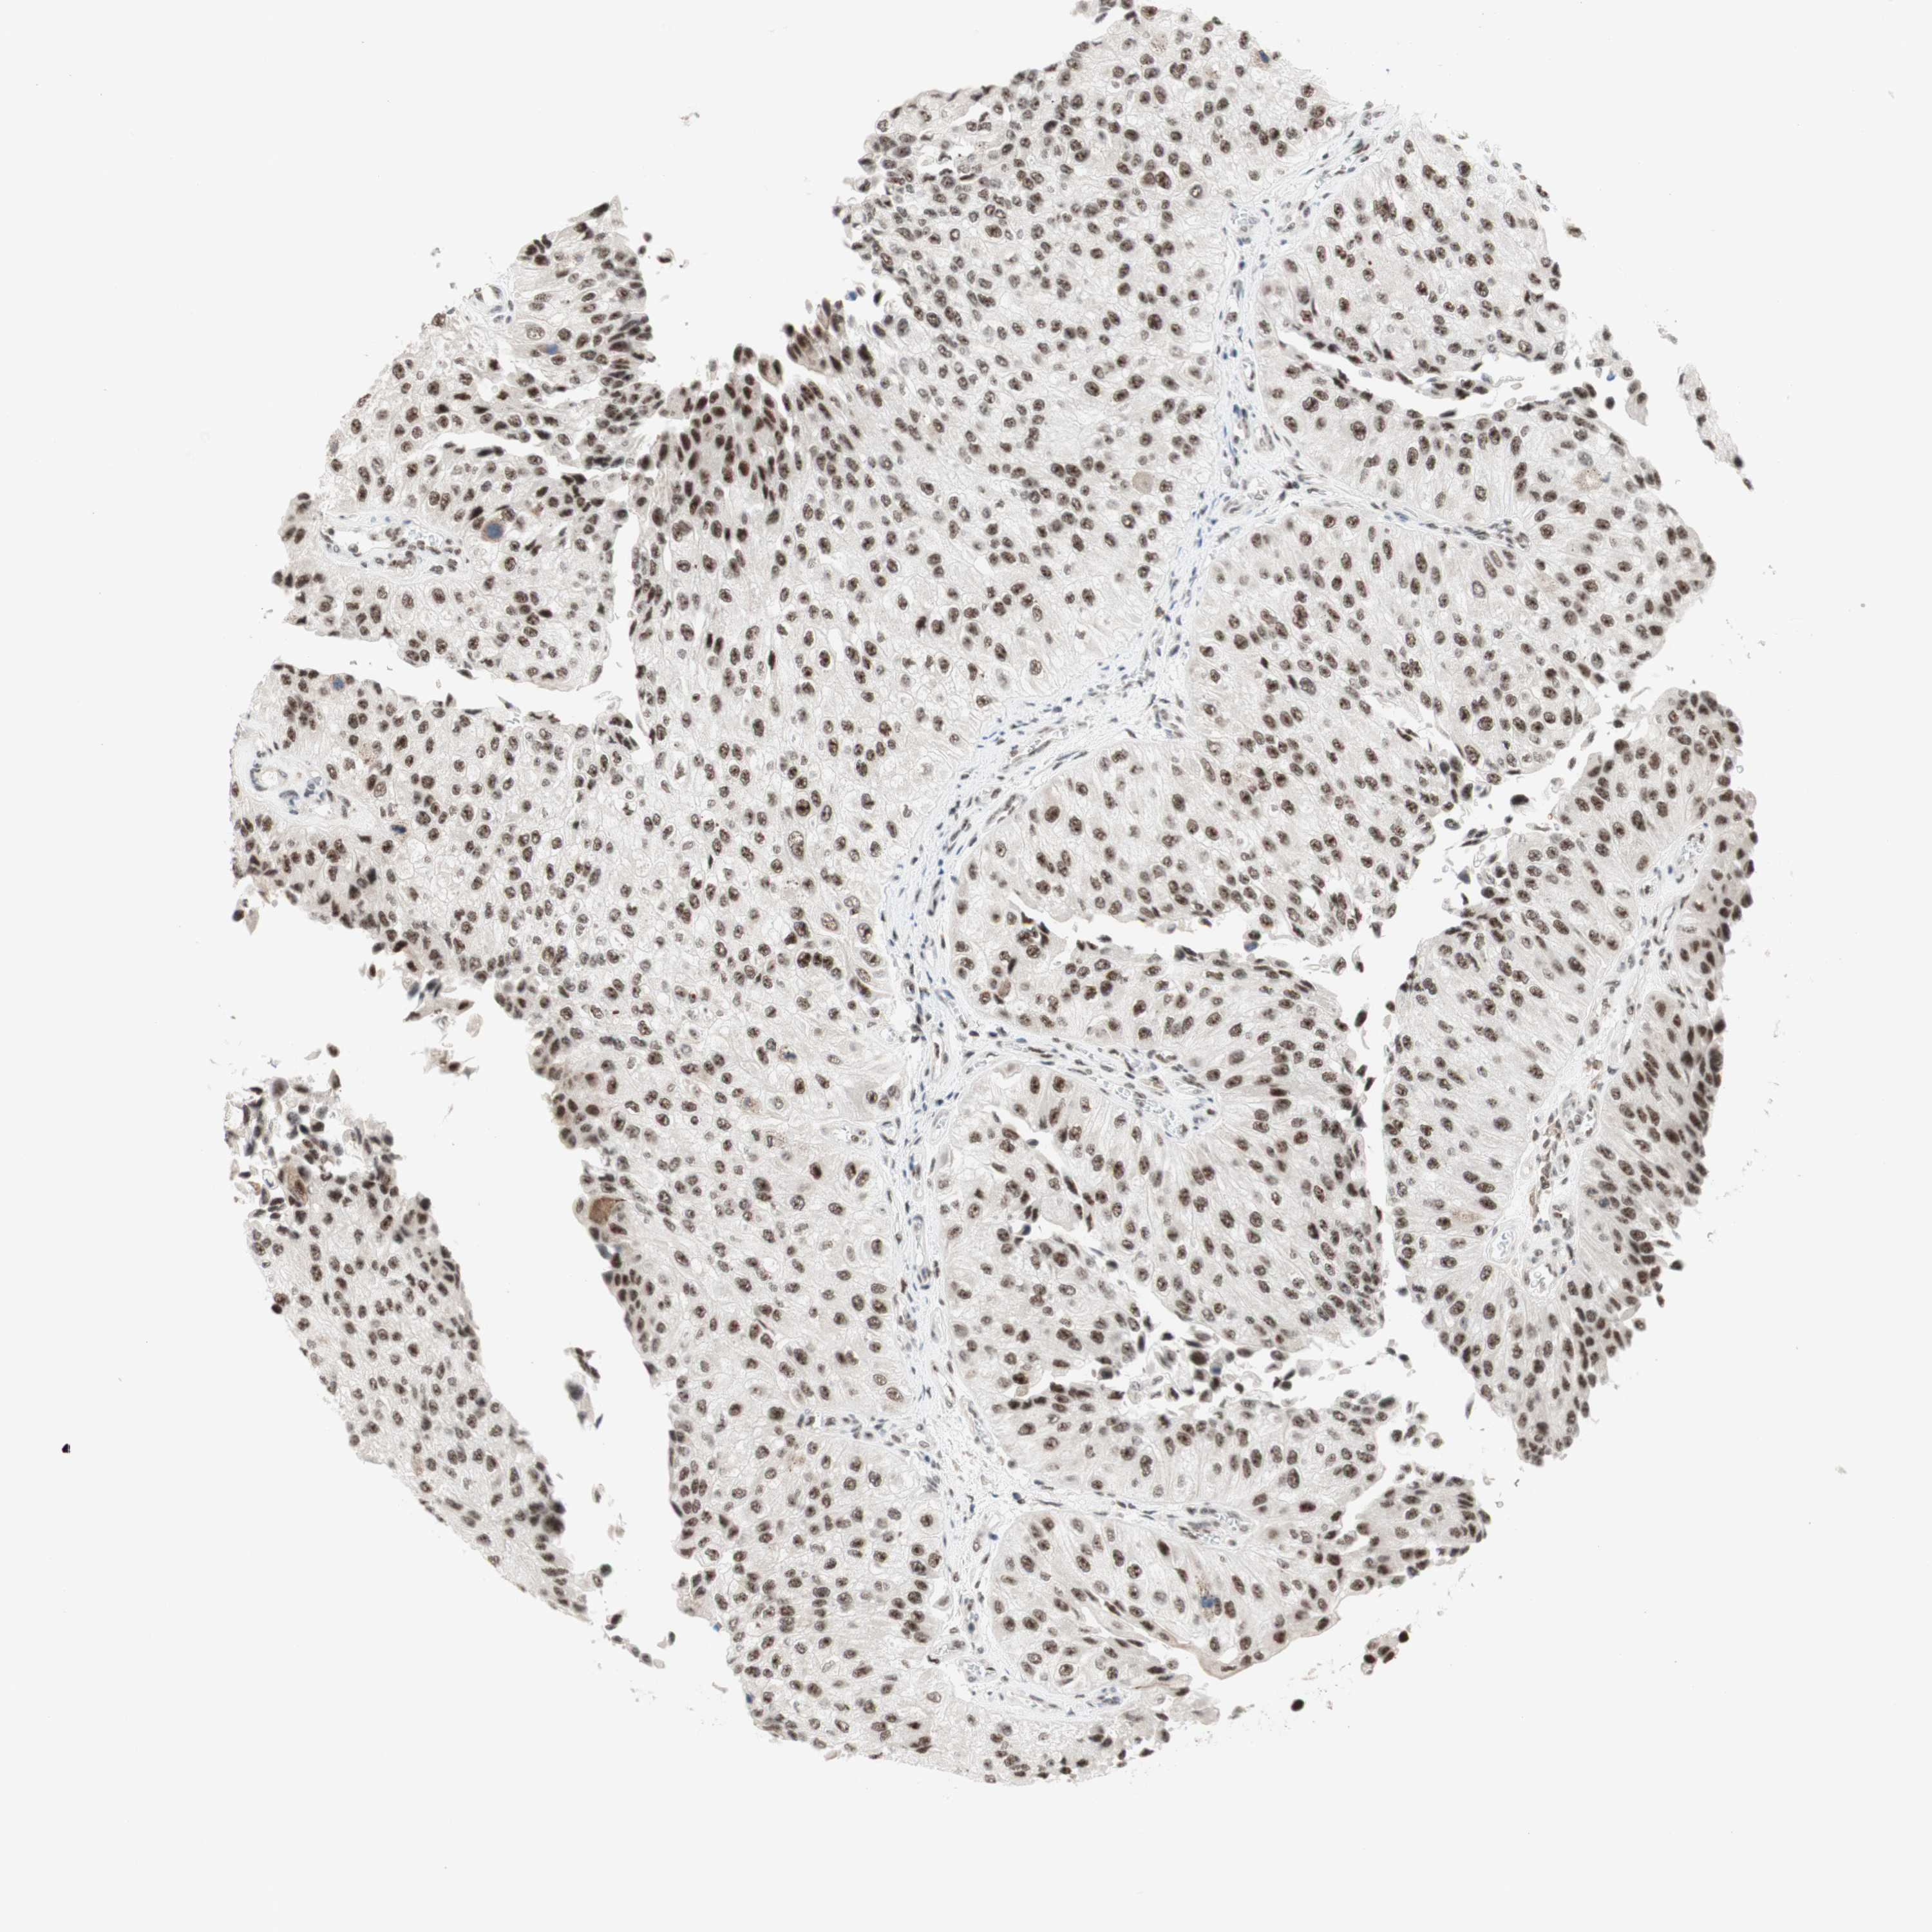

UROTHELIAL CANCER - Protein expressioni

A mouse-over function shows sample information and annotation data. Click on an image to view it in a full screen mode. Samples can be filtered based on level of antibody staining by selecting one or several of the following categories: high, medium, low and not detected. The assay and annotation is described here.

Note that samples used for immunohistochemistry by the Human Protein Atlas do not correspond to samples in the TCGA dataset.

Antibody stainingi

Antibody staining in the annotated cell types in the current human tissue is reported as not detected, low, medium, or high, based on conventional immunohistochemistry profiling in selected tissues. This score is based on the combination of the staining intensity and fraction of stained cells.

Each image is clickable and will lead to virtual microscopy that enables deeper exploration of all samples and also displays staining intensity scores, fraction scores and subcellular localization as well as patient and tissue information for each sample.

Antibody HPA038051

Antibody HPA059070

Antibody CAB012448

Staining

High

Medium

Low

Not detected

Intensity

Strong

Moderate

Weak

Negative

Quantity

>75%

75%-25%

<25%

None

Location

Nuclear

Cytoplasmic/membranous

Cytoplasmic/membranous,nuclear

Urothelial carcinoma, High grade

Urothelial carcinoma, Low grade

Urothelial carcinoma, NOS